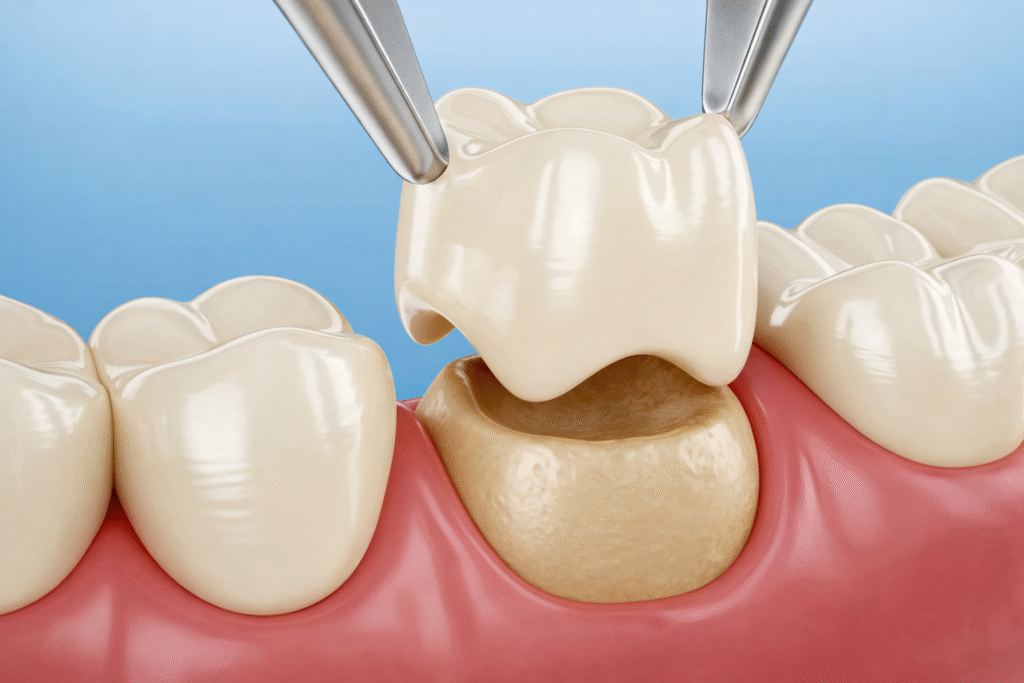

Oral and Maxillofacial Surgery is a specialized branch of dentistry that focuses on the diagnosis and surgical treatment of a wide range of conditions affecting the mouth, jaw, face, and neck. Additionally, It encompasses procedures such as teeth extractions, dental implants, corrective jaw surgery, and facial trauma or pathology treatment. Our Oral and Maxillofacial surgeon at Share A Smile Dental Clinic in Pandalam and Pathanamthitta is here to bring back your smile!

Jaw Deformities and Facial Aesthetic Surgeries

Developing abnormal jaw growth can cause protruding chins, gummy smiles, inability to chew, tongue thrusting, sleep apnoea, and lisping. Therefore, camouflage treatment can control and manage the deformity without surgery with the right intervention. If the deformity is too obvious and extensive, it’s better to have a maxillofacial surgeon and orthodontist work together.